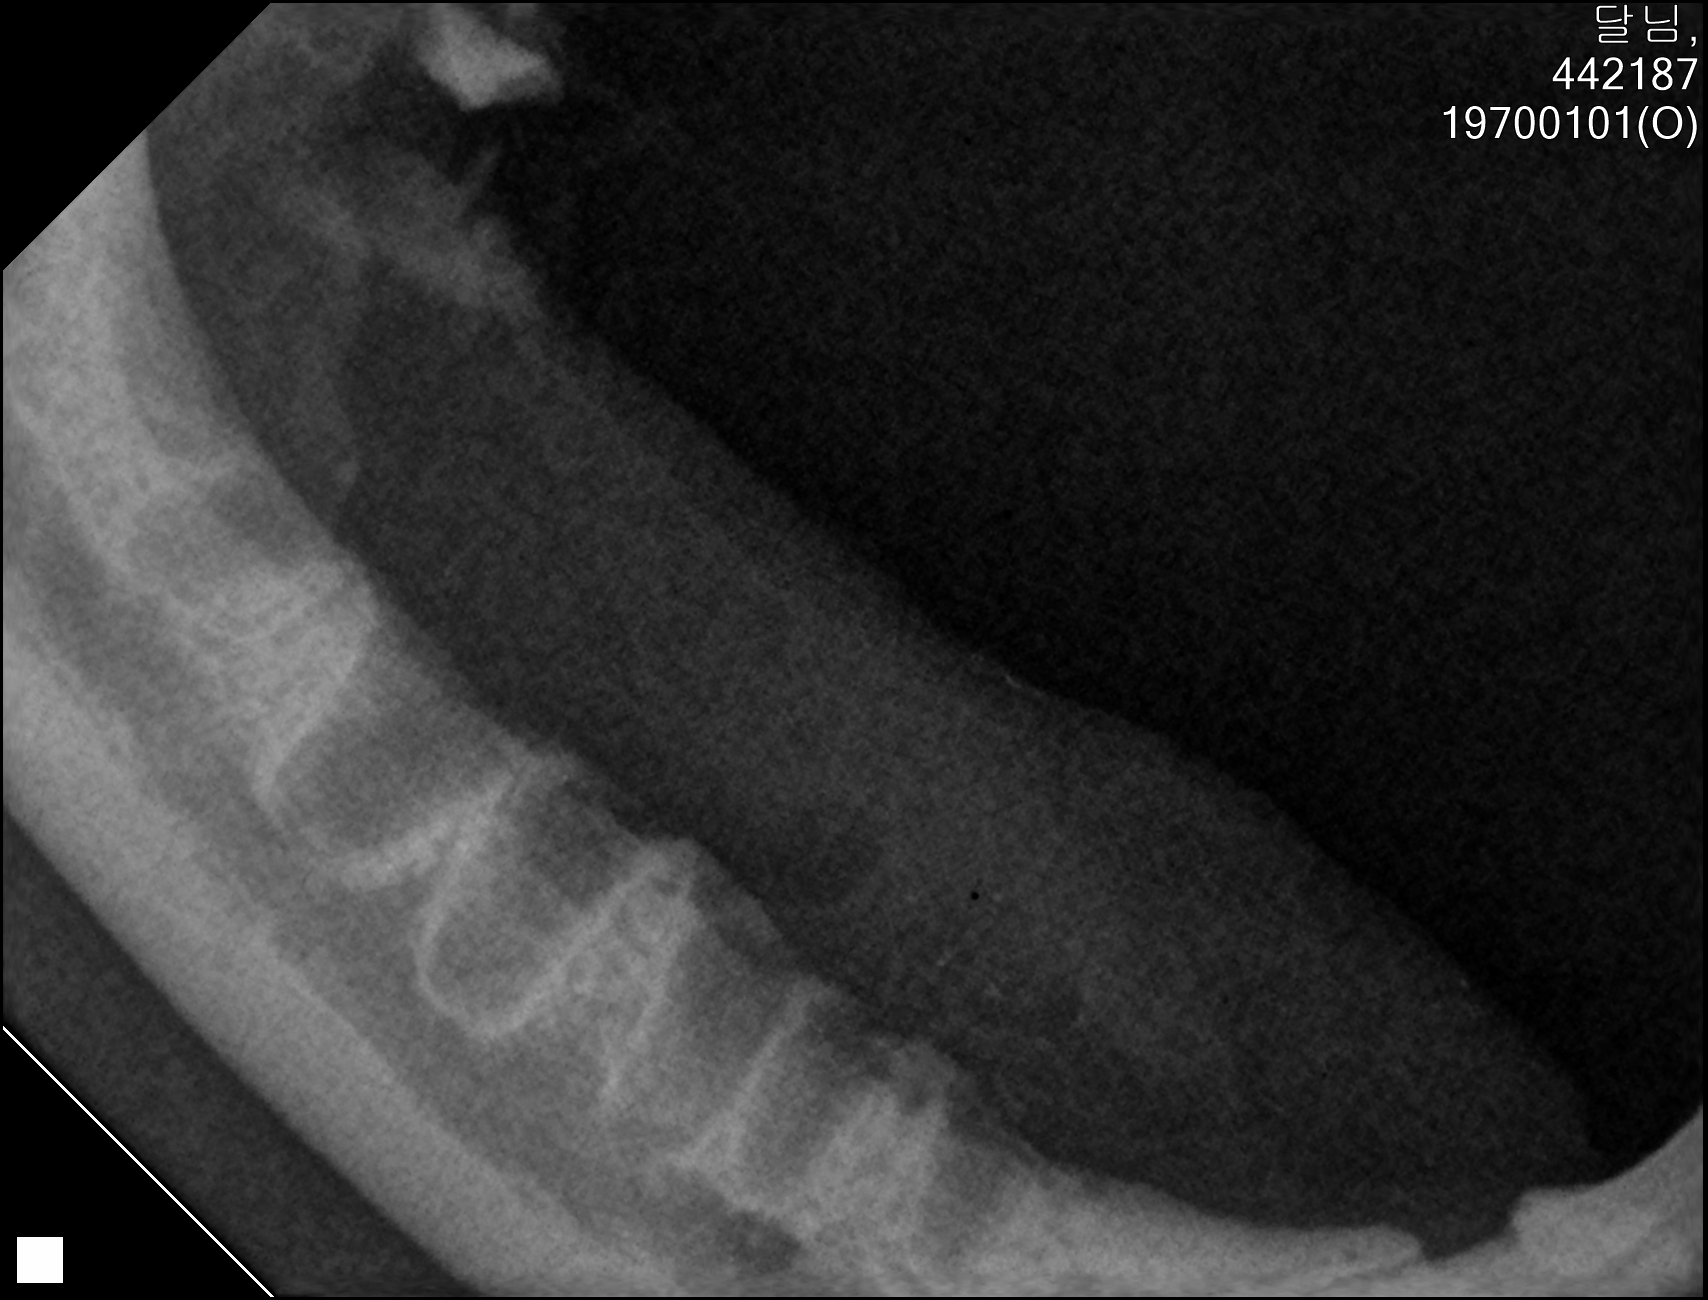

| 치료과정 | 달님이를 병원에 데려갔을때 거의 한달 가까이 먹질 못했기 때문에 몸무게는 2키로 초반대로 나갔고 마취하고 검사할수있는 상태가 아니였기 때문에 피검사를 통해서 간단히 검사후 입원하기 시작했습니다 탈수증세가 너무 심했고 수액을 맞으면서 자발식을 찾으려 했지만 달님이는 전혀 먹질 않았고 입원기간도 길어지게 되었습니다 그 와중에 청천벽력같은 소리를 듣게되었습니다 신장수치가 좋지않아 신부전이라는 결과였습니다 손도안타는 이아이를 제가 과연 케어할수있을까 너무 너무 걱정이였고 눈물이 앞을 가렸습니다 하지만 우선 체력을 회복한후 걱정은 나중에 하기로하고 달님이 치료에 집중하기 시작했습니다 병원에서도 선생님들이 달님이를 강제 급여도 해주고 수액도 계속 맞고 보니 꽉 막혀있던 코에서 콧물도 나고 소변도 보기 시작했습니다 그리고 다시 검사를 하고나니 다행히 신부전은 아니고 지방간이라고 하였습니다 아마도 오래전부터 먹는양이 줄어들었고 최근에 들어 아예 먹질못해서 간이 망가졌고 황달증세가 생겼다고합니다 어떤 이유에서인지모르겠지만 달님이는 원래 호흡기도 안좋았고 항상 콧물과 재채기를 달고산 아이라 호흡기도 안좋았고 이빨상태도 안좋아 밥을 못먹기 시작했던거같습니다 우선 체력회복이 중요하기때문에 집에서 케어한후 간 회복후 추후에 발치를 하기로 하였습니다 집에 온후 달님이는 바로 사료를 먹기시작했습니다 아마도 병원이 싫어서 밥을 안먹었던 모양입니다 매일 처방식과 약을 먹이면서 살을 찌우기 위해 이것저것 달님이가 좋아하는 캔과 츄르를 바치기 시작했고 다행히 달님이는 매일 맛있는 밥을 먹으며 살이 찌기시작했습니다 한달되는 날 발치와 검사를 위해 병원에 가서 검사를 하였는데 달님이는 3.86키로로 몸무게도 상당히 늘었으며 검사결과 모든 수치가 좋아졌습니다 그리고 마취후 이빨상태를 보니 치주염이 심각했고 이빨은 어금니부터 송곳니까지 다 내려앉은 상태였습니다 입안은 구내염이 시작되었고 원장님은 송곳니도 지금도 안좋지만 나중에 되면 더 아퍼질꺼라며 전발치를 해야한다 하였고 저는 달님이과 전발치를하고 길에서 잘 살수있을까 너무 걱정이였지만 나중에 아파서 또 구조후 마취하는것보다 낫다고 생각했고 밥자리도 잘 되어있어 전발치하고도 잘사는길냥이들 많다고 들어서 전발치를하게되었습니다 달님이는 수술을 잘 마쳤고 퇴원후 달님이는 집에서 10일정도는 약먹고 회복해야하기때문에 집에서 좀더 케어한후 방사할 예정입니다 |